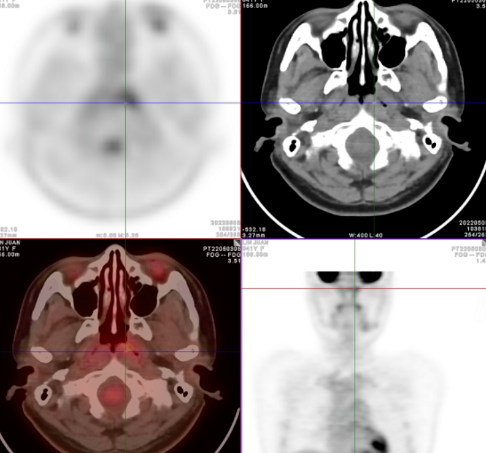

Fig.1左侧颈部Ⅱ区多发FDG摄取增高增大淋巴结 SUVmax8.3,大者约22mm×14mm

Fig.2舌下腺区FDG摄取增高灶SUVmax6.9

Fig.3鼻咽左侧咽隐窝后壁稍增厚,FDG摄取增高SUVmax3.4

Fig.4子宫内膜区FDG摄取增高,SUVmax7.0(月经期)

● 病例2:反复多次多点活检,未发现原发肿瘤,原发灶隐匿